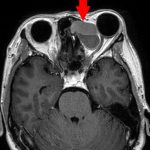

No.’23_132 手術前1

No.’23_132 手術前2

No.’23_132 摘出 前

No.’23_132  摘出 中

No.’23_132 摘出 後